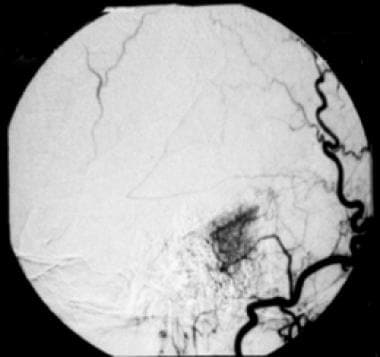

右枕动脉选择性血管造影显示通过耳动脉的局灶性高血供。早期和延迟染色见于小脑桥脑角脑膜瘤,是典型的“婆婆征”的特征。